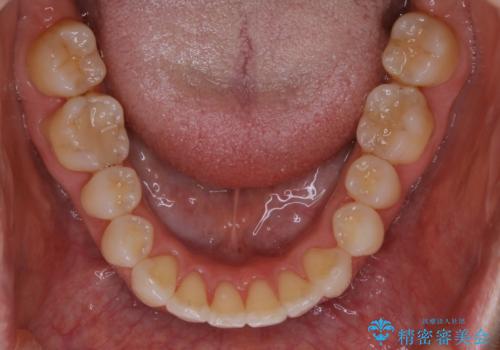

- 下の前歯のがたつきが気になるとの事でご相談にいらした患者様です。

元々はリンガルブラケットをご希望されていましたが、モニター制度を利用してインビザラインによる治療を行いました。

インビザラインFULLで奥歯の噛み合わせから改善させることで、上下の真ん中位置をしっかり合わせることが出来ました。

横顔のシルエットも改善させることができ、大変喜んでいただけました。